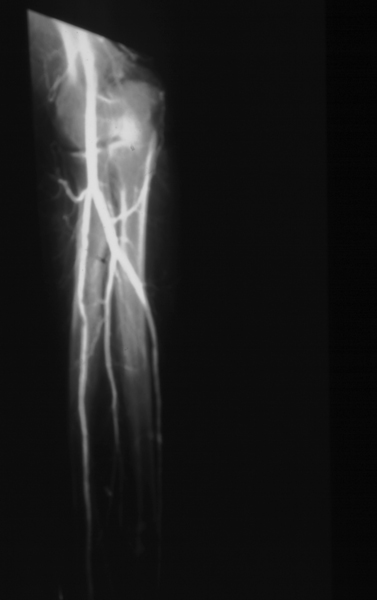

Radiology MS 42 - AP Left Brachial Angiogram

Identify: brachial, radial, ulnar, common interosseous, ulnar recurrent, radial recurrent